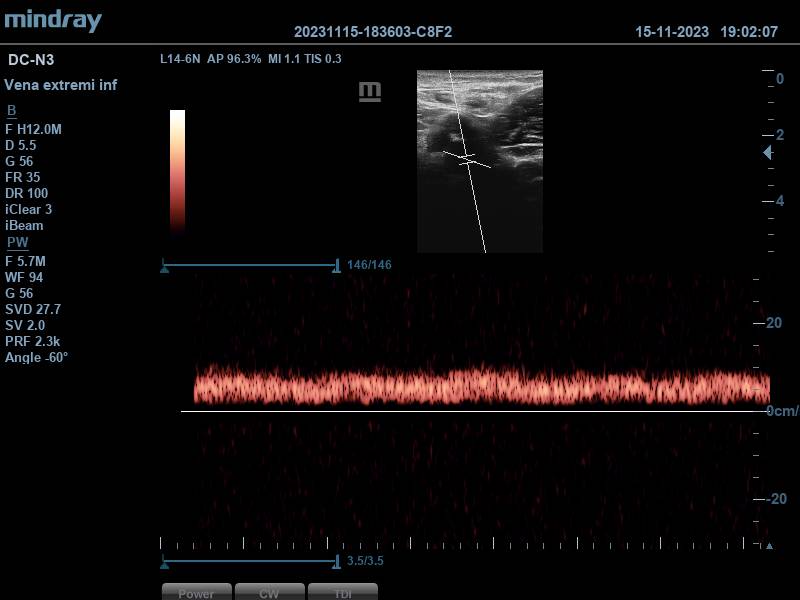

Se aplica Doppler pulsado, obteniéndose dos espectros compatibles con vasos arteriales (correspondientes a la arteria femoral superficial y femoral profunda), y otros dos espectros con patrón sugestivo de flujo venoso, que aumenta con la compresión del gemelo, generando picos de flujo. Todo ello, hace pensar en que estamos ante una duplicidad femoral.